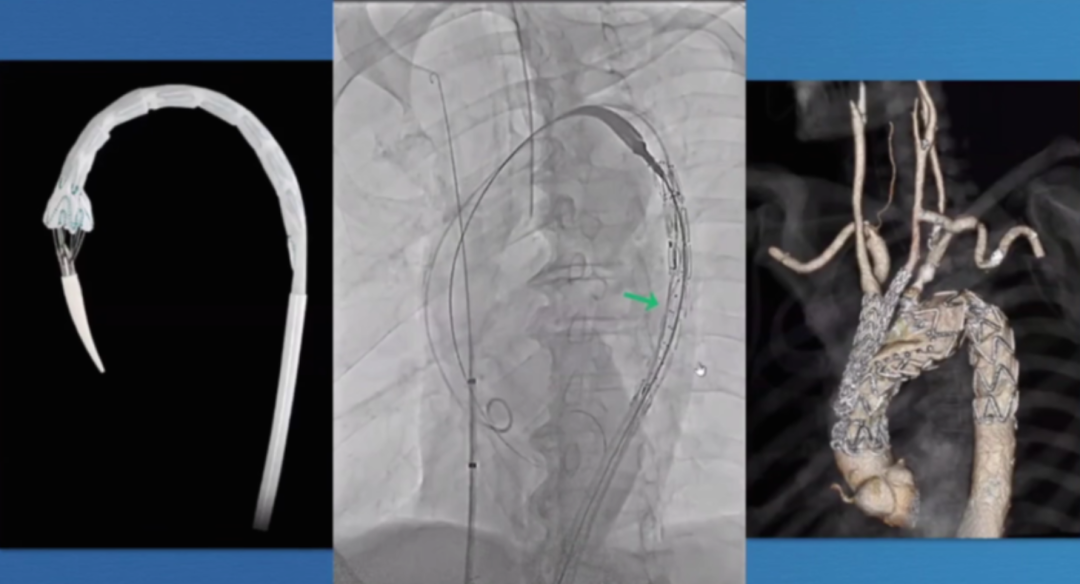

在近端密封区选择上,通常需向近端延伸25-30mm以实现更优密封效果,而定制器械凭借开窗设计,能有效增加密封长度。定制化支架技术也至关重要,支架必须精准定位,标记移动易引发开窗错位;同时要做好旋转控制,否则支架旋转不良会提升逆行夹层风险。一旦出现开窗对齐问题,可能导致I型内漏,且长期处理难度大,需借助更复杂的穿通技术纠正分支位置。

第二代分支支架在设计上进一步优化,Cook LSA分支支架(Gen2)采用三角形凹槽设计,要求左颈总动脉与左锁骨下动脉间距25mm,分支开口与织物端距离60mm,其预装导管系统使分支接入更简便,为临床操作提供了便利。

在主动脉介入治疗领域,支架设计持续创新。Terumo双分支支架采用大型矩形凹槽设计,即便旋转90度,仍能顺利接入分支,对于弓部曲线较为紧张的情况适配性更强。不过,该支架也面临技术挑战,手术中需要精准控制支架的旋转与对齐,以确保治疗效果。

深圳设计的支架同样亮点十足。它具有短输送尖端的特点,无需跨越主动脉瓣,部署过程简单,且不需要进行严格的血压控制。支架配备两个平行侧支,搭配低剖面8-9F桥接支架,在接入方式上,采用右臂入路结合左颈动脉小切口的方式,为手术操作提供了便利,也有望为患者带来更优的治疗体验。

郑永强教授对主动脉弓修复进行总结,提出基本原则:尽可能向近端延伸(Z0/Z1),避免仅在Z2锚定(密封常不充分),单开窗选择有限,现成单分支支架是可行选择,而核心教训是必须在假体/健康主动脉段锚定,这一结论为临床实践提供了重要的指导原则,推动主动脉弓腔内修复技术向更安全、更有效的方向发展。